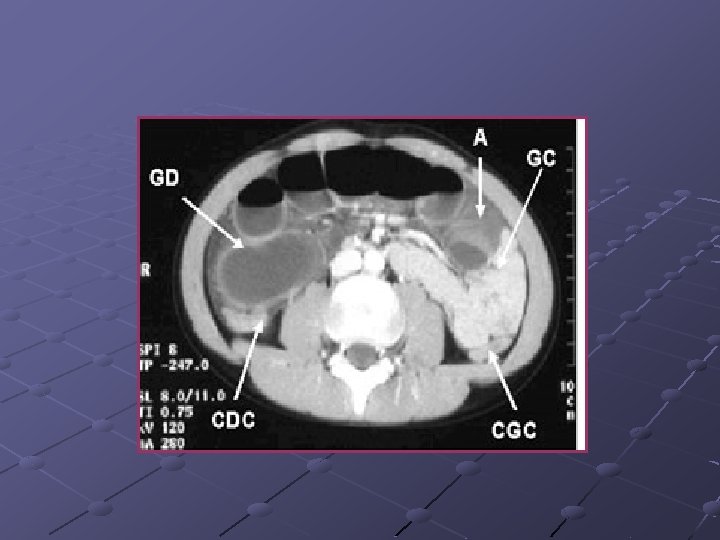

Cas n° 3 Garçon de 19 ans Pas d’antécédents particuliers Douleurs et distension abdominales, vomissements Examen distension diffuse, pas de signes de péritonite

« northern exposure sign » « coffee bean sign »

Volvulus du colon sigmoïde Cause fréquente de volvulus( segment long et mobile) ASP couché ( « coffee bean sign » ) pose le diagnostic dans 80% des cas Origine congénitale ou défaillance des moyens de fixité du colon ttt: décompression endoscopique suivie d’une résection élective